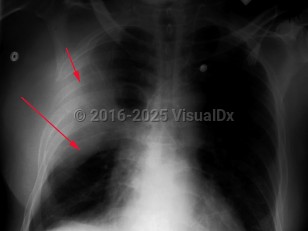

Klebsiella pneumonia

Klebsiella pneumonia is caused by Klebsiella pneumoniae, an enteric gram-negative rod. Klebsiella pneumoniae usually enters the lung via aspiration of oral secretions and can result in both community-acquired pneumonia as well as hospital-acquired pneumonia. Most cases occur in the hospital.

The onset of symptoms is sudden with pleuritic chest pain, chills, prostration, moderate fever, dyspnea, and productive cough. The sputum can be thick and bloody, greenish, and also have a "currant jelly" appearance. The white blood cell count is usually elevated, but neutropenia appears to be frequent in those with cirrhosis and Klebsiella infection. Bacteremia can occur in up to 25% of cases. Complications can include lung abscesses, pericarditis, empyema, and meningitis. Rarely, there can be eye complications. In hypervirulent cases, pyogenic abscesses can form in the liver, central nervous system, urinary tract, soft tissues, and other sites.

The onset of symptoms is sudden with pleuritic chest pain, chills, prostration, moderate fever, dyspnea, and productive cough. The sputum can be thick and bloody, greenish, and also have a "currant jelly" appearance. The white blood cell count is usually elevated, but neutropenia appears to be frequent in those with cirrhosis and Klebsiella infection. Bacteremia can occur in up to 25% of cases. Complications can include lung abscesses, pericarditis, empyema, and meningitis. Rarely, there can be eye complications. In hypervirulent cases, pyogenic abscesses can form in the liver, central nervous system, urinary tract, soft tissues, and other sites.